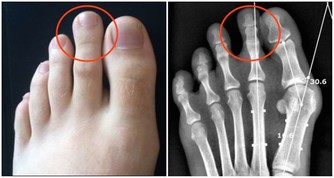

腳部出現青筋

腳面部位本來是平坦無皺紋的,如果表面出錢青筋凸起,說明腳部的血液循環開始出現受阻現象。雖然身體暫時感覺不到其他的不適癥狀,但是我們千萬不可以忽視這一癥狀。往往大病之前總是潛伏著一些小毛病。

腳部出現青筋,說明血液循環不暢通,但是前期人體並不會出現其他不適應的癥狀。沒有出現不適,不代表完全沒問題。血液循環不暢通,將會導致心臟部位無法及時接受身體回流的血液,繼而影響下一輪供血;還會導致腳部功能退化,出現足部組織壞死的現象。

所以,腳部出現青筋一定要引起註意,防患於未然總是疾病最好的對手。